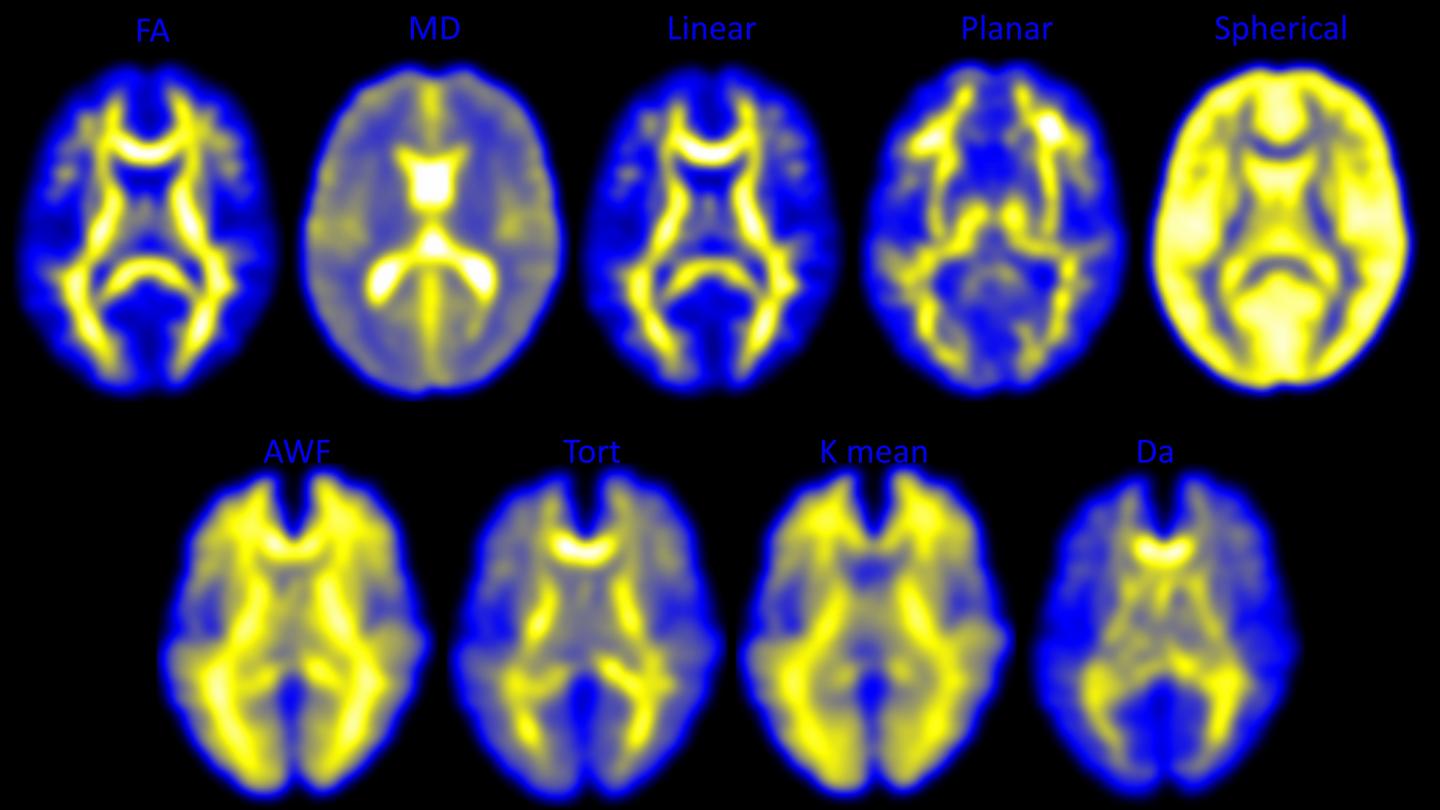

In the study, each player underwent pre- and post-season imaging: a specialized MRI scan, from which diffusion tensor imaging (DTI) and diffusion kurtosis imaging (DKI) data were extracted to measure the brain's white matter integrity, and a magnetoencephalography (MEG) scan, which records and analyzes the magnetic fields produced by brain waves. Diffusion imaging can measure the structural white matter changes in the brain, and MEG assesses changes in function.

The research team calculated the change in imaging metrics between the pre- and post-season imaging exams. They measured abnormalities observed on diffusion imaging and abnormally increased delta wave activity on MEG. The imaging results were then combined with player-specific impact data from the HITS. None of the 24 players were diagnosed with a concussion during the study.

Players with greater head impact exposure had the greatest change in diffusion imaging and MEG metrics.

"Change in diffusion imaging metrics correlated most to linear acceleration, similar to the impact of a car crash," Dr. Davenport said. "MEG changes correlated most to rotational impact, similar to a boxer's punch. These results demonstrate that you need both imaging metrics to assess impact exposure because they correlate with very different biomechanical processes."